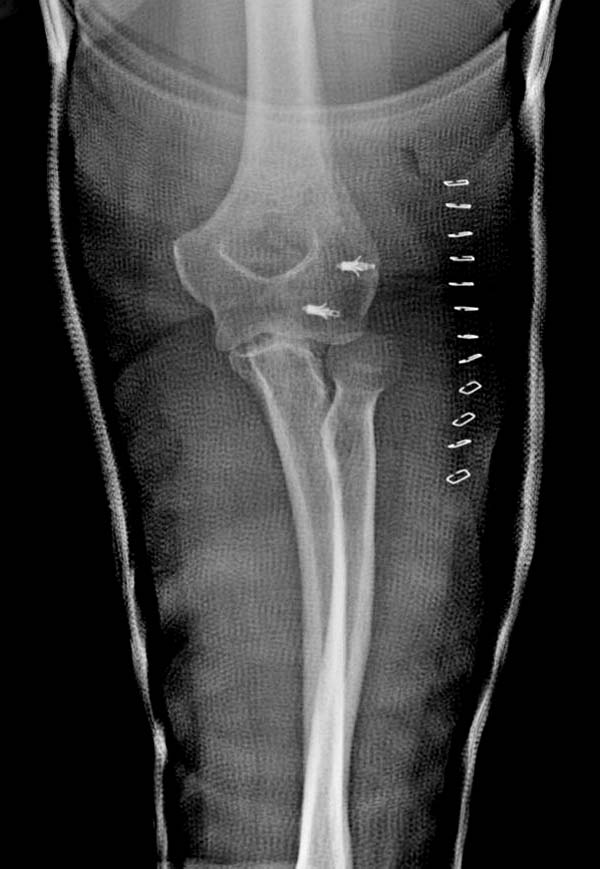

В заключение: результат применения трансартикулярной фиксации (более 20 лет) в сравнении со сложными реконструктивными операциями показывает лучшую амплитуду движений! Возможно, у коллег имеются другие варианты, а мы без привлечения больших затрат решаем проблему.

Для примера здесь случай начатый в другом центре, а потом переправленный к нам.

Снимки: 1-2 вывих, 4-5 вторичное смещение в гипсе, реконструкция латеральной связки и капсулы 13-14, повторный вывих после реконструкции, перевод в наш центр; 18-21 временная фиксация, 22-25 трансартикулярная фиксация и нестабильная головка фиксирована спицами, 29-30 амбулаторно, 32-33 после удаления винта и спиц...